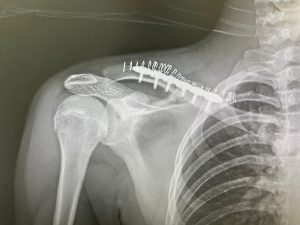

La intervención, realizada por el Dr. Antonio Manuel Alvarado Bonilla en el Hospital HLA Jerez Puerta del Sur, consistió en la reconstrucción del músculo y la colocación de una placa de fijación en el hombro derecho, ya que presentaba una rotura con desplazamiento de la clavícula. La operación resultó totalmente satisfactoria, evaluándose por parte de los doctores en unos dos meses el período de recuperación.